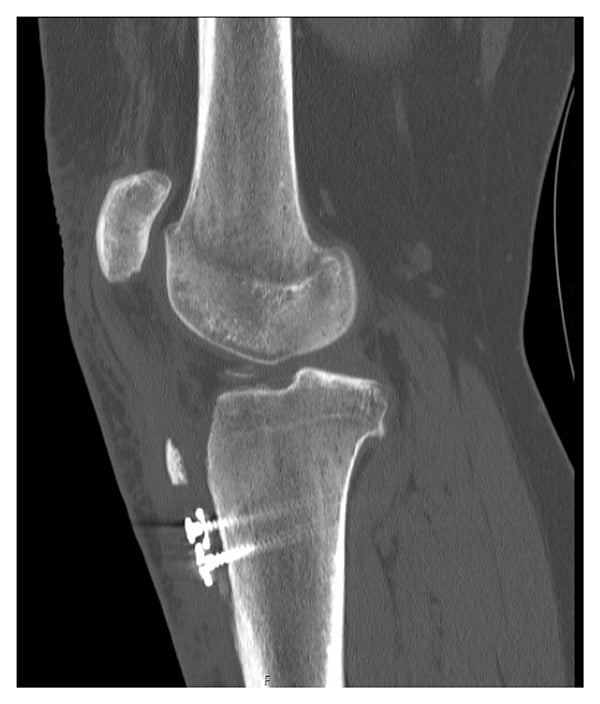

A 16-year-old female lacrosse player presented to the clinic with left knee pain. She reported no traumatic injuries and said she had suffered 2 previous noncontact lateral dislocations: at age 11 and at age 13. A year prior, she had undergone a tibial tubercle osteotomy (TTO) combined with a medial patellofemoral ligament (MPFL) reconstruction and particulated cartilage implant to the patella and trochlea. The patient reported quadriceps weakness with difficulty ambulating. Physical examination revealed anterior knee crepitus with range of motion, 3/5 quadriceps strength, and tenderness to palpation over the tibial tubercle. Computed tomography (CT), magnetic resonance imaging (MRI), and X-ray of the prior TTO revealed fragmentation of the tibial tubercle shingle and patella alta, as indicated by a Caton–Deschamps ratio of 1.5 (Figure 1).

Figure 1: Lateral left knee CT image prior to TTO revision surgery.